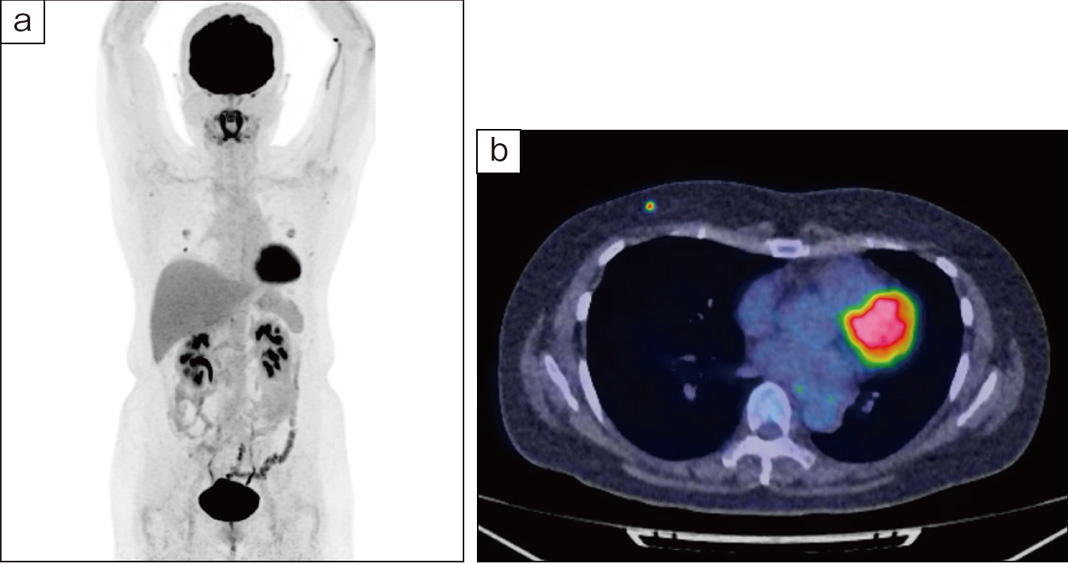

図2 FDG-PET

a:MIP画像 b:fusion(axial)画像